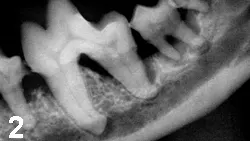

Physical Examination. Local disease is often obvious; signs include gingivitis, calculus, gingival recession, pocket formation, mobile teeth, missing teeth, bleeding upon probing, purulent debris in the sulcus, and halitosis (Figures 1 and 2).

Figure 2: Radiograph of the left mandible of the patient in Figure 1.

Profound bone loss surrounds the roots of the premolars and molars. The patient's activity level dramatically improved after surgical correction with full mouth extractions.